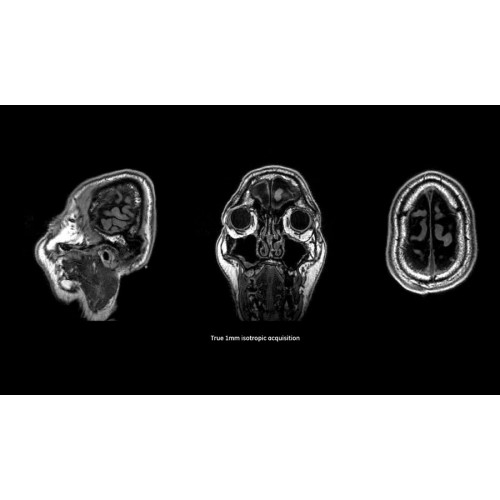

МРТ аппарат GE SIGNA Voyager 1.5T позволяет проводить полный спектр магнитно-резонансных исследований, включая нейровизуализацию, исследования опорно-двигательного аппарата, органов брюшной полости и малого таза, а также специализированные кардиологические программы.

• Неврология и нейрохирургия